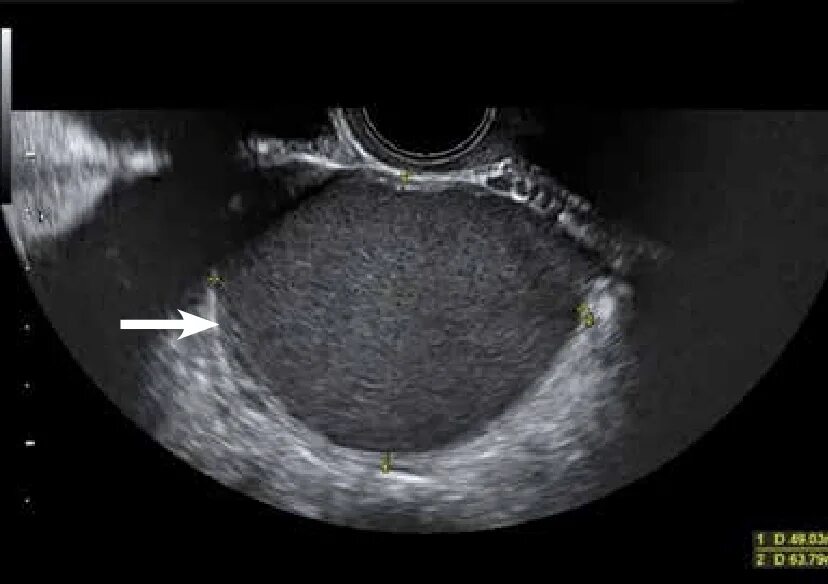

Почему увеличена матка после